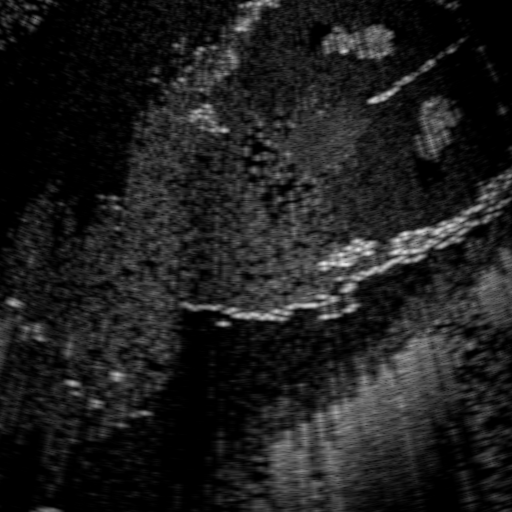

Qualitative Results. Fig. 3 shows a visual comparison of the three model variants on four examples. The baseline L2HM fails to preserve anatomical structures due to missing structural information in the input images. Resulting ambiguities in the network prediction cause artifacts such as blur in regions that feature fine details such as bones. Providing segmentation maps as additional input (L2HMS) greatly reduces such artifacts as shown in Fig. 3(c). However, L2HMS still struggles in modeling complex non-local features such as directional occlusion artifacts, note the lack of acoustic shadows in Fig. 3(c). In contrast, our final model L2HMSA is able to accurately synthesize these features and produces translations significantly closer to the target, as demonstrated in Fig. 3(d). In particular, our proposed model with segmentation and attenuation integral maps is able to recover both missing anatomical structures and directional artefacts.

Above image translation has been demonstrated on patches. For the entire field-of-view (FoV) US images, patch fusion from image translation of non-overlapping patches would cause artifacts at image seams. Averaging overlapping patches, on the other hand, would blur the essential US texture. Although seamless tiling of US images is possible using graphical models [3], this requires prohibitively long computation time. Herein, we instead directly apply our trained generator on full FoV low-quality images, since the generator is fully convolutional and thus can operate on images of arbitrary size. Fig. 4 shows two examples of translated images by L2HMS and L2HMSA, demonstrating direct inference on full FoV images. While anatomical structures are well preserved and the effect of attenuation integral map is apparent, speckle texture appearance is seen to degrade slightly especially in the top image regions, where the ultrasound texture looking particularly different due to focusing difference and near-field effects.

(a) Input

(b) L2HM

(c) L2HMS

(d) L2HMSA

(e) Target